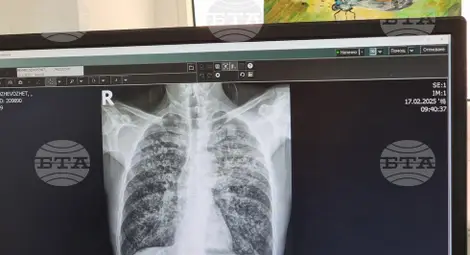

Безплатни прегледи за туберкулоза ще се извършват в Ямбол идната седмица, трима са заболелите в региона от последните дни

От началото на тази година в област Ямбол с регистрирани 18 случая на туберкулозна инфекция. От тях три са от последните дни – 23-годишна жена и децата ѝ – на 11 месеца и на 4 години, които в момента се лекуват в болница в София, каза за БТА директорът на Регионалната здравна инспекция д-р Радостина Калчева.